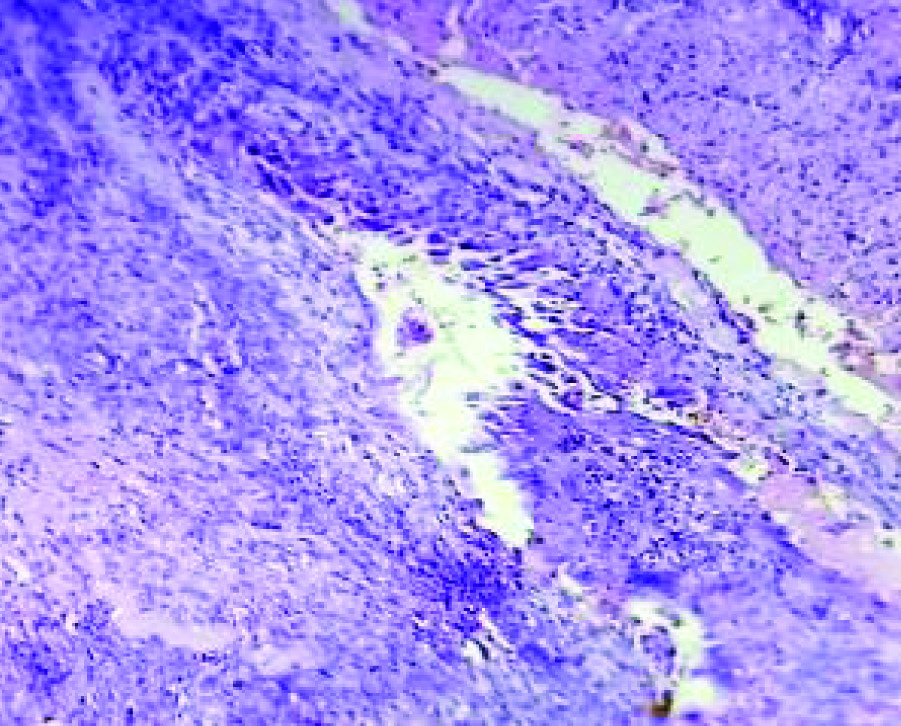

Sections from the uterus showed secretory phase of endometrium [Table/Fig-1] with pre-decidualized stroma. No Arias-stella reaction identified. Both fallopian tube showed normal histology. Sections from right ovary showed cyst wall lined by endometrial glands and stroma and sheets of haemosiderin laden macrophages [Table/Fig-2,3]. The glands exhibited typical Arias-Stella reaction focally with enlarged hyperchromatic irregular nuclei, some of which showed hob-nail pattern [Table/Fig-4,5 and 6]. Sections from the left ovarian cyst showed haemorrhagic corpus luteum.

(H&E, 10X) Cyst wall focally infiltrated by sheets of haemosiderin laden macrophages.

(H&E, 40X) Showing haemosiderin laden macrophages.